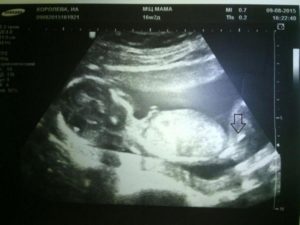

Можно ли на 16 неделе беременности узнать пол ребенка

Безусловно, самым точным методом определения пола будущего любимого чада является УЗИ.

Проблема лишь в том, что УЗИ можно проводить на определенных сроках беременности, не более трех раз (на 13-й неделе, на 23-24 неделе, непосредственно перед родами).

Вывод: УЗИ – самый точный метод, но он тоже дает осечку. Срок беременности, развитие малыша, уровень специалиста, точность оборудования, положение ребенка в животике на момент проведения исследования – все эти важные факторы могут повлиять на результат.

Важно! Гениталии малыша формируются на 11-й неделе. Но в самом начале формирования пениса у мальчика это скорее небольшой бугорок, чем полноценный орган, который легко заметить.

Только к 13-й неделе он вытягивается в длину и становится более осязаемым. На раннем этапе их развитие настолько незначительно, что перепутать пол ребенка очень легко.

К 19 неделе хороший специалист уже сможет на 80% быть уверенным в том, кто у мамы в животике: мальчик или девочка. Мальчика определить проще, а если вы ожидаете девчушку, то лучше обратиться к узисту уже на 24-й неделе беременности.